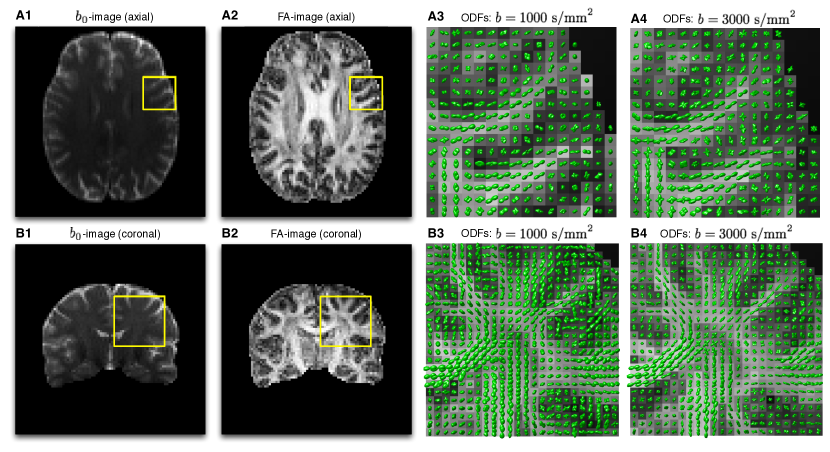

Refer to caption

Figure 9. (Subplots A1-A2) b0subscript𝑏0b_{0}-image and FA images of an axial slice of an in vivo scan used for presentation of experimental results; (Subplots A3-A4) ODFs corresponding to the localized region indicated by the yellow squares in Subplots A1-A2 for b=1000𝑏1000b=1000 s/mm2 and b=3000𝑏3000b=3000 s/mm2, respectively; (Subplots B1-B2) b0subscript𝑏0b_{0}-image and FA images of a coronal slice from the same scan; (Subplots B3-B4) ODFs corresponding to the localized region indicated by the yellow squares in Subplots B1-B2 for b=1000𝑏1000b=1000 s/mm2 and b=3000𝑏3000b=3000 s/mm2, respectively.

As the next step of our experimental study, real-life estimation has been performed using in vivo diffusion data (see Section 5.1). For the sake of the clarity of visualization, we restrict demonstration of the obtained reconstructions to 2-D views (aka “slices”), two examples of which are depicted in Fig 9. In particular, Subplots A1-A2 of the figure display an axial slice of the acquired b0subscript𝑏0b_{0}-volume and its corresponding fractional anisotropy (FA) image, respectively, while Subplots B1-B2 show a coronal slice from the same 3-D volume along with its associated FA image, in the same order. Additionally, Subplots A3-A4 of Fig. 9 show the ODFs corresponding to the localized regions indicated by the yellow squares in Subplots A1-A2 for the case of b=1000𝑏1000b=1000 s/mm2 and b=3000𝑏3000b=3000 s/mm2, respectively. (To facilitate the analysis, the ODFs are shown over the background of their associated FA values.) Analogous results pertaining to the coronal view are shown in Subplots B3-B4 of the figure. It should be noted that, in both cases, the ODFs have been computed by means of the FRACT algorithm of [65], which seems to provide a reasonable balance between the robustness of more traditional QBI [25] and the high resolution gain of its solid-angle formulation [27].